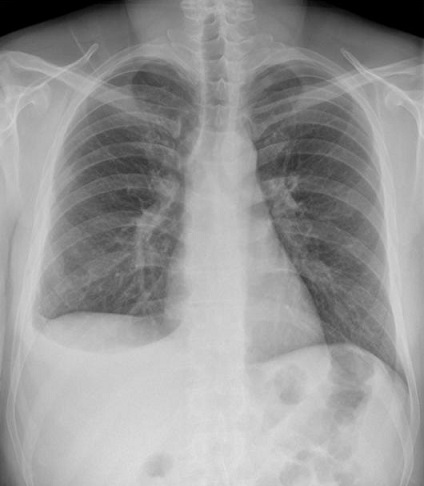

Image radiologique d'une epachement

pẻripherique enkyste ou localise du poumon

gauche . Aspect radiologique

est opacite

en forme de " goutte d'eau "à

contour nette , homogene

et n'a pas de bronchogramme

aerique , situe à inferieur du poumon gauche .

Image radiologique standanisee pulmonaire , cliche

de face PA |

Aspect

radiologique d'une epanchement enkyste , loclise du

poumon droit en coupe de face et de propile droit .

Image radiologique en forme de " goutte d'eau " est

tres nette sur coupe de profile . Image radiologique

tomographie ( planigraphie ) pulmonaire , coupe de

face et de profile à travers la lesion |